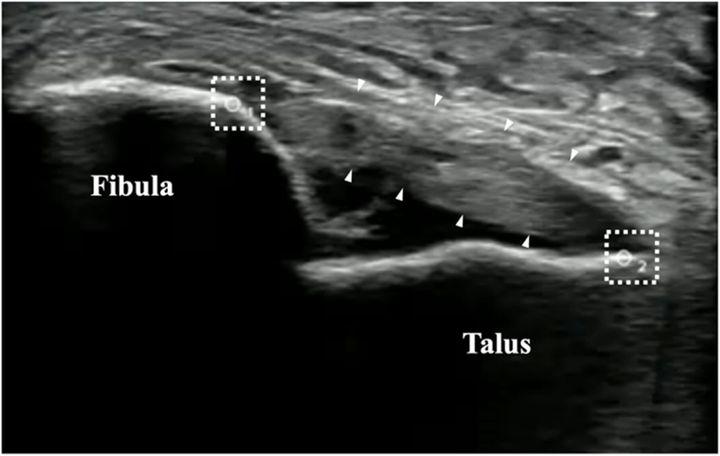

“たかが捻挫”を覆すエビデンス / 図はエコーで観察した捻挫直後の足首(超音波画像)。白い枠で示した腓骨(Fibula)と距骨(Talus)の間隔が、靭帯のゆるみ(関節の不安定性)を表します。時間の経過とともにこの距離は縮まっていき、靭帯が回復する様子を捉えることができます。/Credit:Yuto Uchida et al . Journal of Experimental Orthopaedics (2025)

本研究では、まず「足首をひねった直後」の患者さんを対象に、その靱帯の回復の様子を超音波検査(エコー)で継続的に測定しました。

具体的には、受傷後の時点で足首にストレスをかけて前後のゆるみ具合を評価する「前方引き出しテスト」を行い、その映像をエコーで撮影しながらどの程度骨と骨の間が開くかを数値化します。

痛みの有無や腫れ具合だけではわかりにくい「靱帯そのものの安定性」を、客観的に捉えられる手法です。